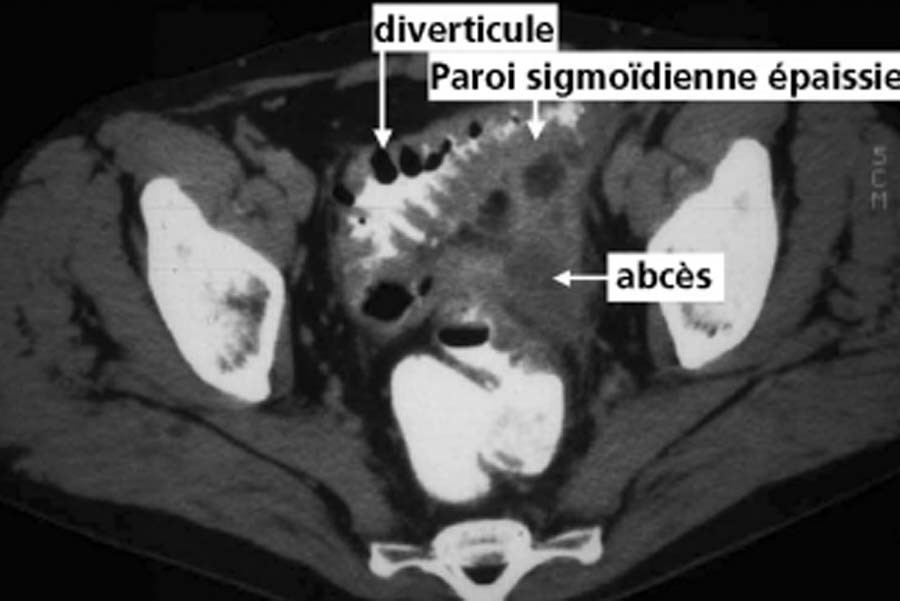

Patient hospitalisée pour douleurs en FIG, fièvre. qu’est ce que c’est?

Diverticulite aiguë sigmoïdienne

Le patient a une diverticulite. Devant persitance fièvre et augmentation du sd inflammatoire à 48h on réalise le TDM suivant. Vu la taille de l’abcès (>5 cm on va dire), quelle CAT?

drainage de l’abcès: ponction percutanée écho ou scanno-guidée; OU drainage chirurgical si percut impossible (avec RDC à distance)